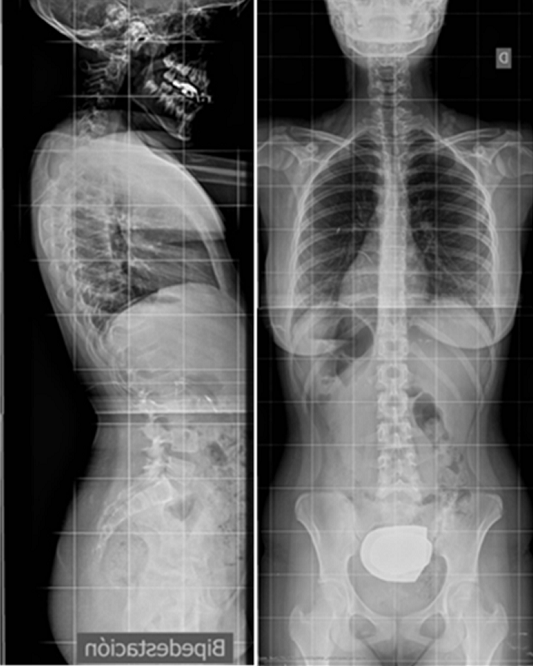

Para evitar la distorsión de las vértebras en esta radiografía, el foco emisor de los rayos X debería incidir en el paciente de anterior a posterior (AP), pues de este modo la columna vertebral está más pegada a la placa receptora. Sin embargo, con frecuencia se realiza en PA para evitar la sobrerradiación del tejido mamario. Sea como fuere, cuando miramos una telerradiografía del raquis la miraremos como cuando examinamos al paciente, desde atrás: la punta del corazón y la cámara del fundus gástrico los veremos a nuestra izquierda (Figura 1). Salvo que la escoliosis clínicamente sea muy evidente, no es necesario hacer una proyección lateral. Se puede dejar a criterio del traumatólogo solicitarla.

Figura 1. Columna vertebral vista desde atrás: la punta del corazón y la cámara del fundus gástrico los veremos a la izquierda. Mostrar/ocultar

La escoliosis puede presentar una o varias curvas y en su evolución, no mejora (Figura 8). Por eso, se hace imprescindible su seguimiento con sucesivas telerradiografías, lo cual obliga, éticamente, a optimizar su estudio8.

Figura 8. Telerradiografía de escoliosis de una paciente a lo largo del tiempo. Mostrar/ocultar